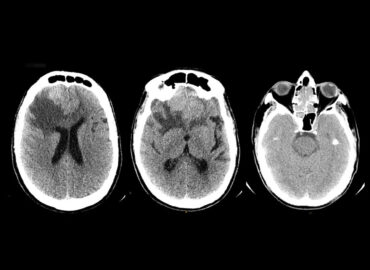

Paciente de 71 años de edad, que consulta por cefalea frontal de 1 mes de evolución, asociada a rinorrea, […]